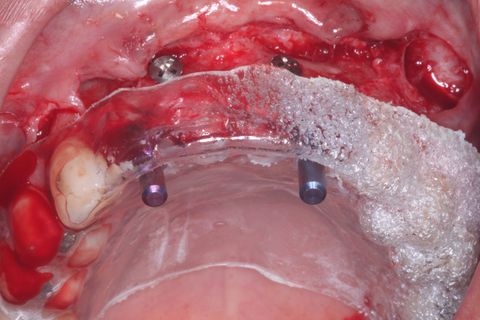

Novo procedimento cirúrgico após 6 mêses. Incisão

Descolamento Mucoperiosteal. Notar o ganho em expessura óssea.

Guia Cirúrgico e paralelizadores conferindo o ângulo de Fresagem/Inserção dos implantes

Implantes Neodent Instalados

Paciente do sexo feminino, 32 anos e 10 mêses de idade, com ausência dos incisivos centrais e laterais superiores, associado a um defeito ósseo vestibular côncavo. Realizamos planejamento reverso, ou seja, enceramento diganóstico prévio para avaliação do defeito ósseo em termos de quantidade e do posicionamento final das próteses. A paciente foi submetido a um enxerto ósseo autógeno do ramo ascendente lado direito e fixação dos blocos ósseos na área receptora, com fixação dos mesmos através de parafusos de fixação com cabeça expandida Neodent. Após 6 meses foram instalados 4 implantes Neodent.